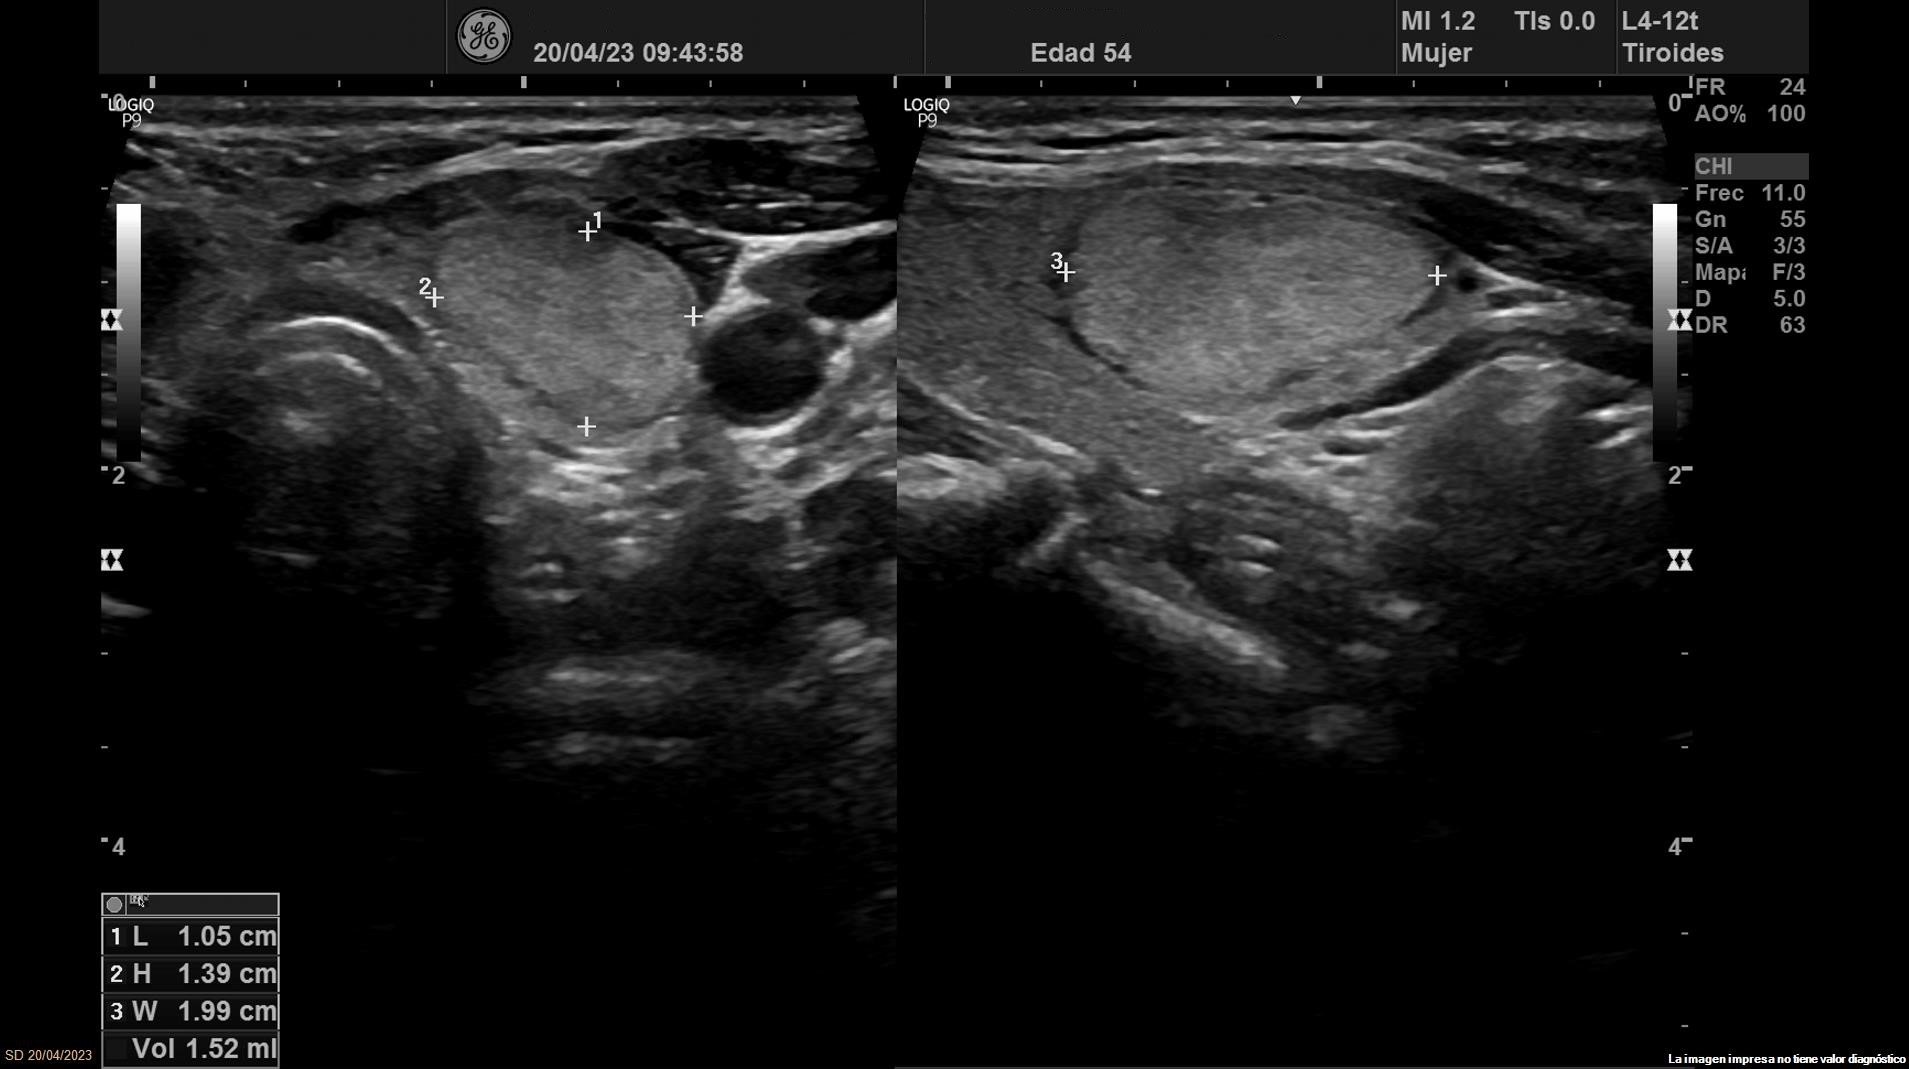

Se objetiva una adenopatía de 0,8 cm de aspecto benigno, ovalada y con bordes definidos. Además, se realiza ecografía tiroidea:

Ante los hallazgos obtenidos, nos planteamos el diagnostico diferencial entre los nódulos tiroideos benignos y malignos. Se deriva a Endocrinología donde realizan nueva ecografía que concuerda con la nuestra.

Se solicita biopsia PAAF obteniendo el diagnóstico definitivo de bocio nodular normofuncionante con estudio citológico de nódulo dominante izquierdo compatible con neoplasia folicular (Bethesda 4).